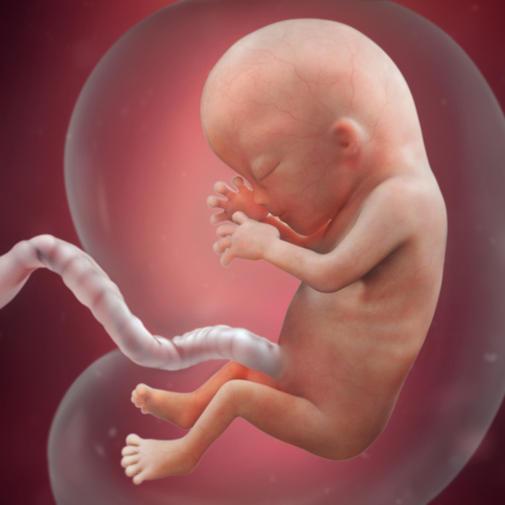

13. týden těhotenství růst tělíčka do délky rychle pokračuje. Hlava se zvětšuje také, ale vzhledem k ostatním částem těla již poněkud pomaleji.

Horní a dolní oční víčka jsou stále spojena. V ústní dutině se pod dásní objevují základy prvních mléčných zubů. Pokračuje vývoj ušního boltce, který se poněkud zvětšuje a má nepravidelně hrbolatý vzhled.

Mění se vzhled přední stěny trupu. Břišní dutina se zvětšuje a pupeční kýla mizí. Poněkud klesá krvetvorba v játrech, krvinky se nyní začínají vyvíjet i ve slezině.

Ledviny začínají produkovat moč, která se vylučuje do plodové vody.

Vstupujete do 4. lunárního měsíce těhotenství. Zvětšuje se obvod pasu i prsou, jste asi o jeden kilogram těžší. Těhotenství na vás začíná být patrné. Vaše miminko dokáže už daleko více věcí – na podnět sevře dlaně, stáhne prstíky na nohách a umí pohybovat rty.

Uši a oči jsou již téměř na svém místě. Chrupavčitý základ kostry se pomalu přetváří na kosti, lze rozeznat i žebra. Ledviny začaly vylučovat moč do močového měchýře, játra tvoří žluč, slinivka břišní vytváří inzulin, střeva se přemisťují dále do těla. Pokračuje vývoj pohlavních orgánů. Děťátko občas zavírá a otvírá pusu, někdy jsou pozorovatelné sací pohyby. Dotvořený krk už může podporovat pohyby hlavičky. Dítě je už schopné vnímat i zvuky díky receptorům vibrací v kůži. Uši se dotváří až v 24. týdnu.

13. týdnem končí 1. trimestr těhotenství. V tomto týdnu měří plod zhruba 7 cm. Při zjišťování délky plodu se měří vzdálenost od temene ke kostrči. Plod nyní váží zhruba 20 gramů.